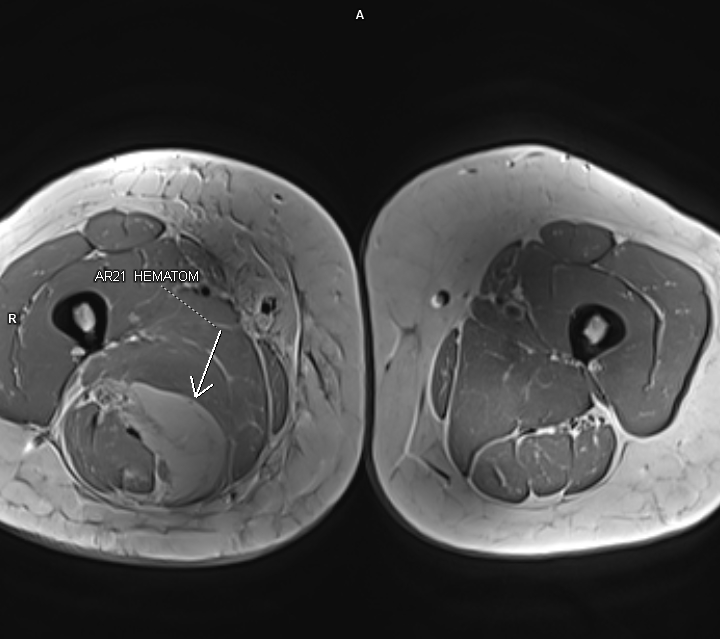

Figurile 5, 6 si 7: axial T1 coapsă bilateral

Discuţie caz nr 92: Harmstring lesion este dificil de tradus în limba română și se referă la leziunea celor trei mușchi ce se inseră pe tuberozitatea ischiadică: semitendinos, semimebranos și biceps femural. Cazul prezentat este a unui pacient care s-a aplecat la cumpărături să ridice o plasa și a simțit o durere puternică în spatele coapsei urmată de impotența funcțională si de creștere de volum a coapsei posterior. Pe imaginile postate se evidențiază avulsia tendonului comun al celor trei muschi ce se regăsește retractat inferior cu formarea unui hematom în vecinătate.